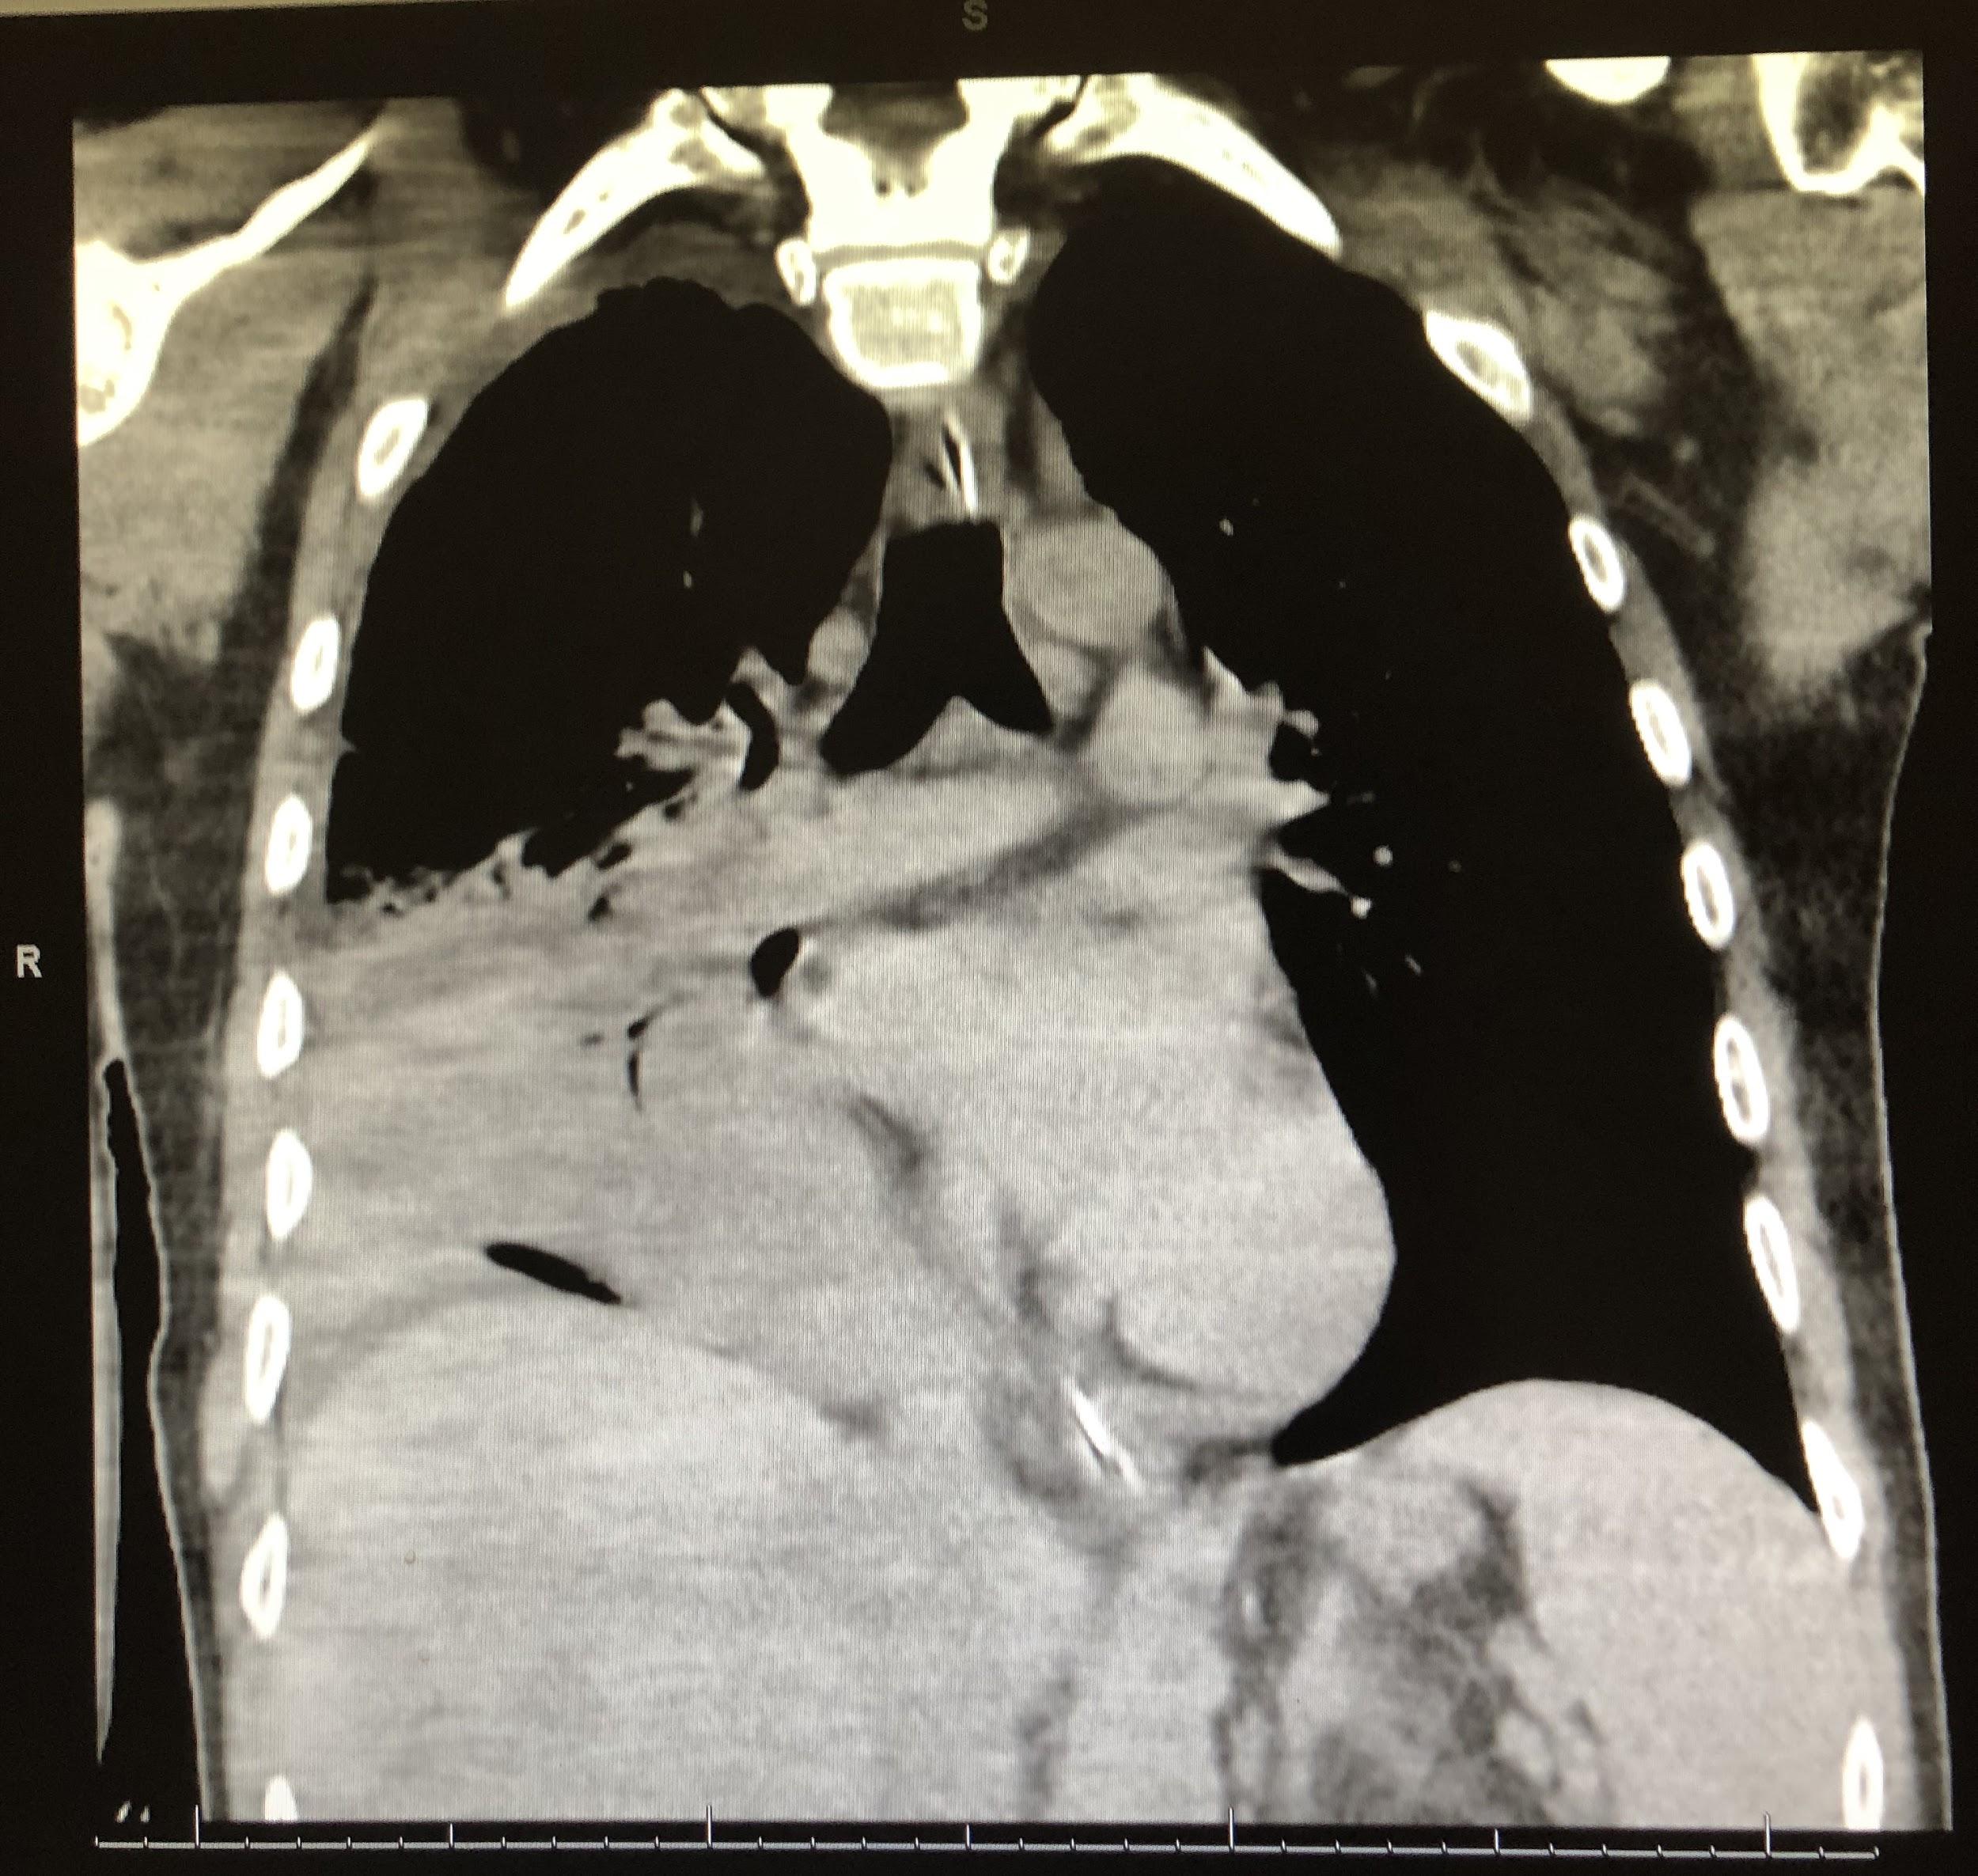

Computed tomography (CT) scans of the chest revealed continued right lower-lobe consolidation and a moderate right-sided pleural effusion (Figure 3). The patient subsequently underwent chest-tube placement, and his clinical status improved; following successful extubation, he was transferred out of the ICU.

Figure 3. CT scans of chest demonstrated a focal area of consolidation in the right middle and lower lobes (top) and moderate right-sided pleural effusion (bottom).